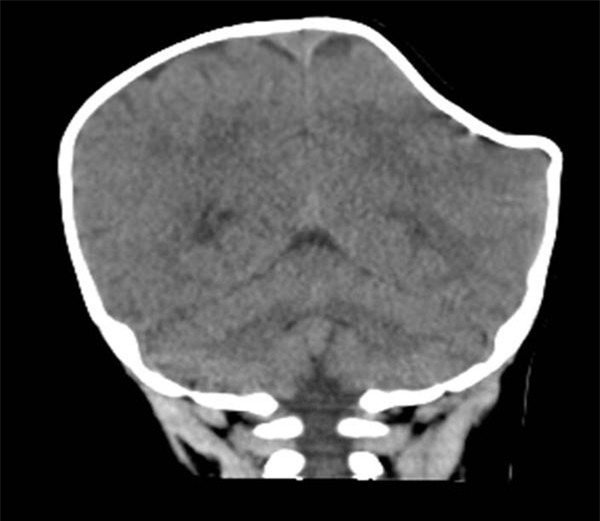

Bác sĩ Hsu Mei-hsin, Bệnh viện Kaohsiung Chang Gung Memorial cho biết, khi bé trai nhập viện, hộp sọ của bé đã bị biến dạng nghiêm trọng. Tuy nhiên, rất may mắn, sau khi chụp cắt lớp vi tính chẩn đoán em bé không có dấu hiệu bị xuất huyết nội sọ. Các bác sĩ đã thực hiện một ca phẫu thuật khôi phục thành công xương sọ của bé trai về vị trí ban đầu, đầu bé đã hoàn toàn bình thường. Bé trai cũng đã tỉnh lại, được xuất viện sau 1 tuần điều trị.

Ảnh chụp cắt lớp đầu bé trai.